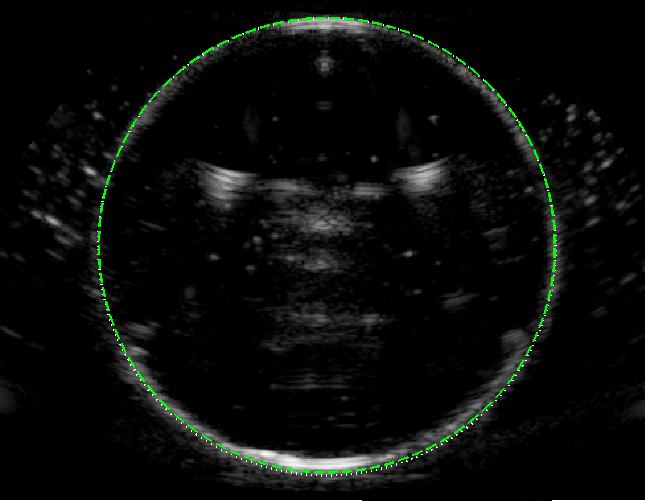

Experimental B-mode images (with curved array) of the circular test object are shown in figure 5, alongside the ray model predictions, for following 3 speed of sound scenarios.

-

(a) : Here we consider m s-1 (ethanol-water mixture) and m s-1 (water), giving . No geometric distortion is evident at the near face but the far face is shifted away from the transducer, in good agreement with the ray model (dashed green line).

(b) : Now taking m s-1 (methanol) gives the more extreme case of . The far-face of the image is highly distorted, in good agreement with the ray model.